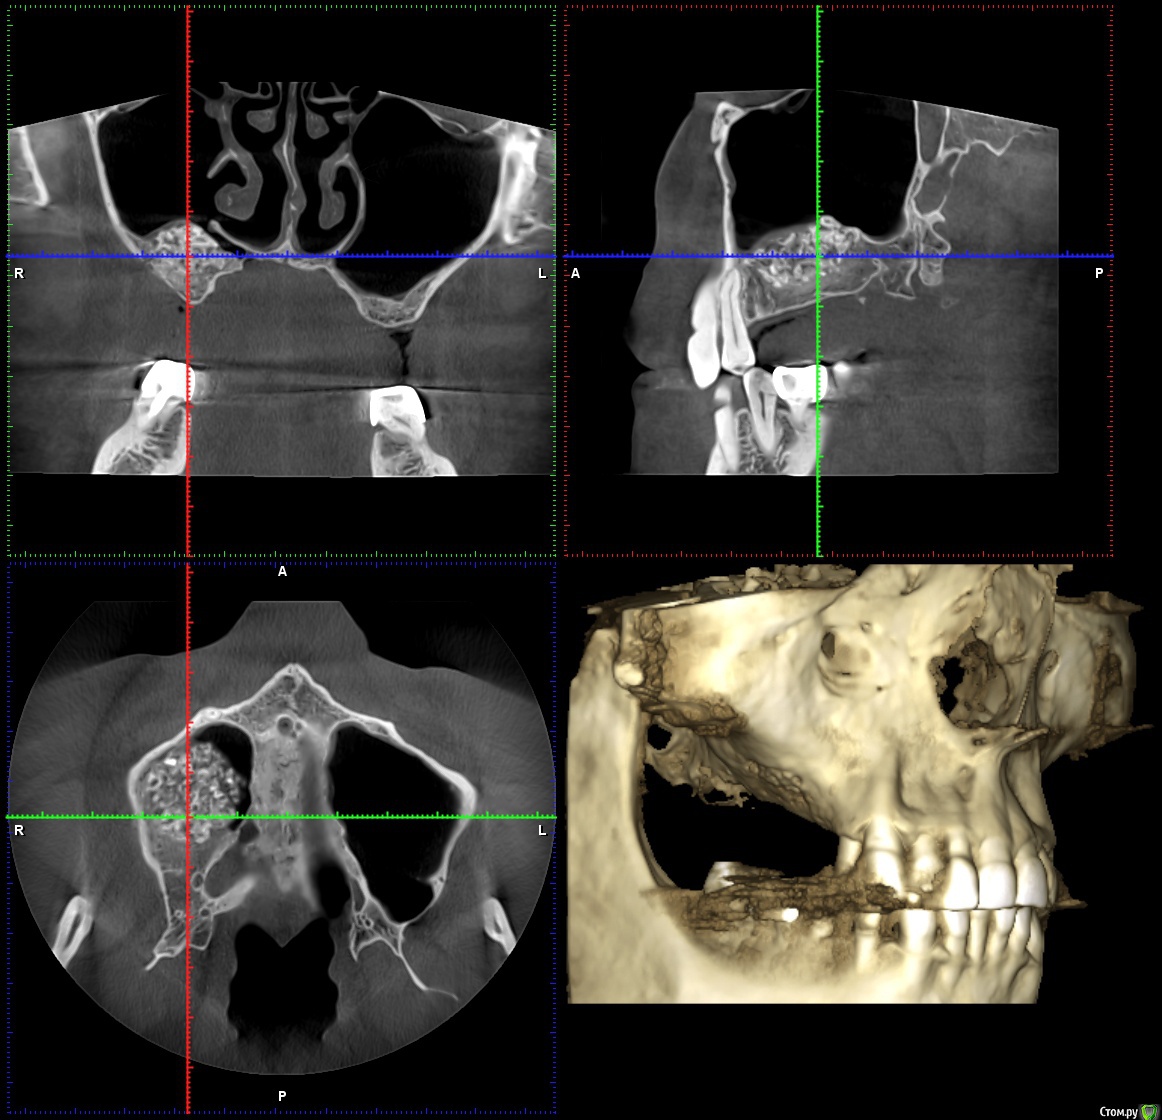

Reyb Опубликовано 14 марта, 2018 Поделиться Опубликовано 14 марта, 2018 Здравствуйте уважаемые доктора.У меня такая проблема,в декабре 2016 года мне делали открытый синус лифтинг справа.Через день-два после операции у меня начались боли,что я воспринял как норму.Дней через 9 врач снял швы,осмотрел и сказал,что всё в норме и боли должны скоро пройти.Через месяц,когда стало можно сморкаться,сразу заметил что справа высмаркивается слизь с кровью,да и к тому же боль не проходила.Пошёл к своему врачу.Он осмотрел и сказал,что всё в приделах нормы (по панорамному снимку).Спустя 1,5 месяца,при сморкании стал замечать ещё и гной с кровью.Спустя ещё где-то 2-3 недели периодически стало закладывать нос.Когда подошло время ставить импланты врач посмотрев КТ сказал,что нельзя,так-как гайморит справа и направил к лору.Пролечившись у лора,стал сомневаться в продолжении имплантации.Спустя 15 месяцев ноющая боль на стороне операции осталась и при сморкании иногда что-нибудь да вылетит из правой ноздри (сгустки крови или почти сухая корка в слизи).На сегодняшний день как и с первых дней после синус лифтинга самочувствие как-будто приболел,писк в ушах(появлялся всегда когда чем-нибудь болею).На КТ просматривается неоднородность и затемнения в материале.Что это,отторжение,инфицирование или норма?К своему стоматологу претензий не имею так-как сделано было на мой взгляд на высоком уровне.Что посоветуете делать в моём случае? КЛКТ от 1.03.2018г.http://my-files.ru/qki4xs Ссылка на комментарий

wladdX Опубликовано 15 марта, 2018 Поделиться Опубликовано 15 марта, 2018 Несколько скринов Ссылка на комментарий

Irouil Опубликовано 15 марта, 2018 Поделиться Опубликовано 15 марта, 2018 Когда КТ делали? У Вас открыт нижний носовой ход в пазуху, уже это одно может вызывать выделения из ноздри, на которые Вы жалуетесь. Да и болевые ощущения, в принципе. Кажется графт не звонил, слизистая спокойная вокруг него, но может быть и не пророс новой костью. Надо готовиться под имплантацию, я считаю, если при сверлении обнаруживается несостоятельность графта - удаление его из пазухи и реоперация через месяц Ссылка на комментарий

Reyb Опубликовано 15 марта, 2018 Автор Поделиться Опубликовано 15 марта, 2018 Когда КТ делали? У Вас открыт нижний носовой ход в пазуху, уже это одно может вызывать выделения из ноздри, на которые Вы жалуетесь. Да и болевые ощущения, в принципе. Кажется графт не звонил, слизистая спокойная вокруг него, но может быть и не пророс новой костью. Надо готовиться под имплантацию, я считаю, если при сверлении обнаруживается несостоятельность графта - удаление его из пазухи и реоперация через месяц Когда КТ делали? У Вас открыт нижний носовой ход в пазуху, уже это одно может вызывать выделения из ноздри, на которые Вы жалуетесь. Да и болевые ощущения, в принципе. Кажется графт не звонил, слизистая спокойная вокруг него, но может быть и не пророс новой костью. Надо готовиться под имплантацию, я считаю, если при сверлении обнаруживается несостоятельность графта - удаление его из пазухи и реоперация через месяцКТ делал 1 марта 2018г. До синуслифтинга выделений не было.Такого чтоб самопроизвольно из носа текло,нет.Только при сморкании бывает,что вылетит не большой сгусток крови. Ссылка на комментарий